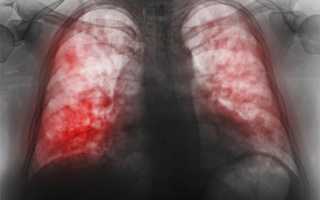

7 самых опасных мифов о пневмонии, которые стоит знать

Миф 1. Пневмония – неопасная болезнь

Не все знают, что в начале XX века 85% людей, заболевших пневмонией, умирали. С открытием антибиотиков ситуация улучшилась, но считать эту болезнь безопасной — серьезная ошибка.

Главный пульмонолог России, академик РАН А. Г. Чучалин, относит воспаление легких к числу самых опасных инфекций на планете. По данным Всемирной организации здравоохранения, пневмония занимает четвертое место среди причин смертности. Даже при легкой форме заболевания 5% пациентов могут погибнуть, а при осложненной пневмонии этот показатель возрастает до 25-50%! Уровень смертности продолжает расти из-за устойчивости бактерий к антибиотикам, и в настоящее время он увеличился еще на 9%.